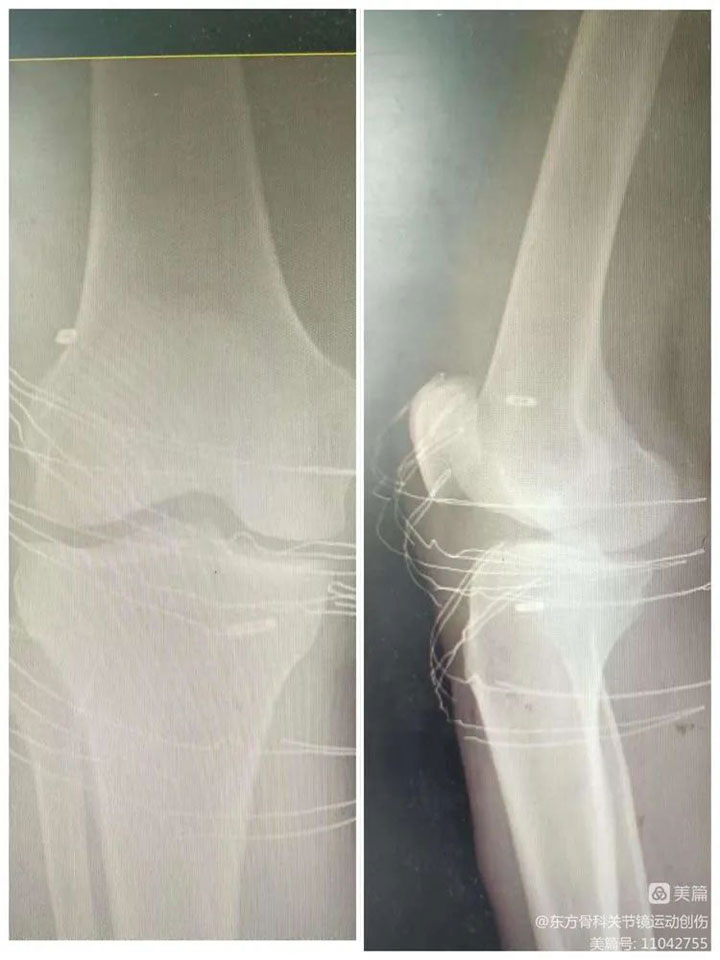

▲术后复查x片,现患者已经康复出院。